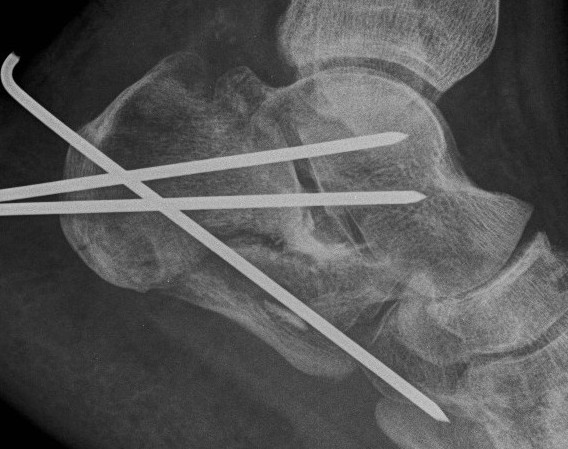

Reduction of varus

- Steinmann pin into tuberosity

- can elevate and pull out of varus